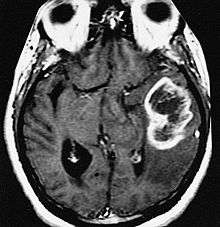

MRI diagnosis is based on lesions that are disseminated in time and space, meaning that there are multiple episodes and consisting of more than one area.[37] There are two kinds of MRI used in the diagnosis of tumefactive MS, T1-weighted imaging and T2-weighted imaging. Using T1-weighted imaging, the lesions are displayed with low signal intensity, meaning that the lesions appear darker than the rest of the brain. Using T2-weighted imaging, the lesions appear with high signal intensity, meaning that the lesions appear white and brighter than the rest of the brain. When T1-weighted imaging is contrast-enhanced through the addition of gadolinium, the open ring enhancement can be viewed as a white ring around the lesion.[38] A more specific MRI, Fluid attenuation inversion recovery (FLAIR) MRI show the signal intensity of the brain. Subjects with tumefactive multiple sclerosis may see a reduction of diffusion of the white matter in the affected area of the brain.[22]